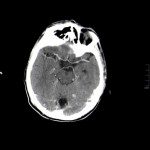

Se visualiza Realce con contraste de varias lesiones nodulares, y “en anillo” de la lesión de mayor tamaño.

Razonamiento: Vemos lesiones captantes nodulares, bilaterales, cerebelosa derecha y occipital y parietal izquierdas, con edema perilesional.